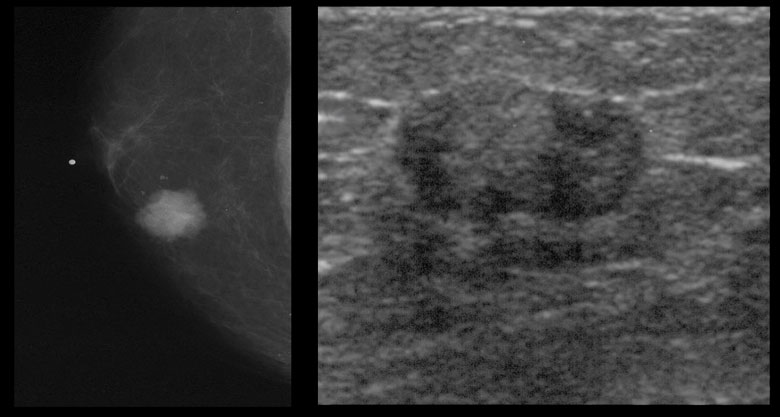

УЗИ молочных желез — информативный и безопасный метод диагностики, с помощью которого можно точно оценить состояние желез, обнаружить доброкачественные и злокачественные образования, уточнить диагноз. Это доступное по цене исследование безвредно и не несет лучевой нагрузки. Оно имеет большое значение в ранней диагностике заболеваний и нередко применяется в профилактических целях. На УЗИ может направить маммолог, онколог, эндокринолог, гинеколог.

Сделать УЗИ молочных желез можно в качестве первичной диагностики и для уточнения уже предполагаемого диагноза. Метод основывается на способности высокочастотных ультразвуковых волн с различной скоростью отражаться от тканей с разной плотностью.

С помощью ультразвуковой диагностики можно обнаружить следующие заболевания:

- воспалительные заболевания — мастит, абсцессы, лактостаз у кормящих женщин, мастопатии различного происхождения и типа — фиброзно-кистозные, диффузные и пр.;

- врожденные аномалии молочной железы;

- рак;

- кисты и доброкачественные опухоли;

Для оценки кровотока в тканях молочных желез используется доплерография. Данные, полученные в результате биопсии под контролем УЗ-аппарата, могут сказать о природе и характере образований в молочных железах.